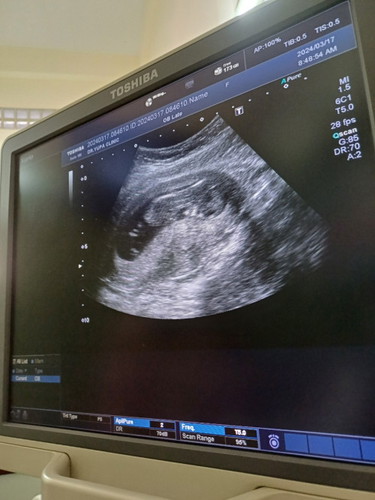

12+5w ค่ะ.

ถุงน้ำคร่ำแบบนี้แคบหรือปกติคะแอบกังวลแถมนอนคว่ำอีกแล้วถ้าน้องโตขึ้นถุงก็จะกลมไหมคะหรือเป็นแบบนี้ ไม่ได้ถามหมอเพราะตื่นเต้นกับการเห็นเบบี๋ค่ะ

ปกติคะ เด็กดิ้นไปทุกๆท่า